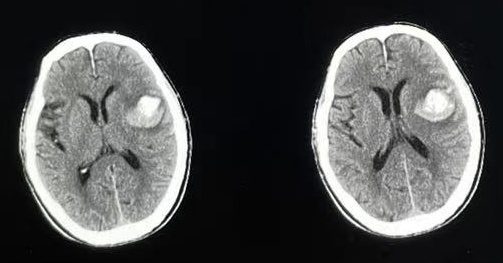

▲术前CT

患者为75岁男性,因突发左侧肢体活动不灵伴失语急诊入院,术前颅脑CT检查提示左侧大脑额颞叶出血,量约20ml,随后收入到神经外科病房。值班医师紧急给予止血 、降血压等一般治疗,并完善各项化验及辅助检查。复查CT显示脑内出血相对稳定,术前检查显示各项指标基本正常,经过团队集体讨论,决定为患者实施微创治疗。